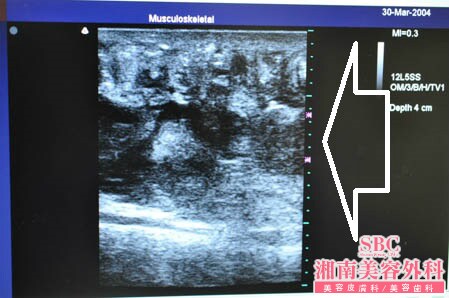

患者様は医療関係者様ですから

超音波の有用性を肌身で日常業務のなかで

実感していらっしゃいますので

今回の脂肪吸引でも超音波、3Dタッチビューを

用いることにしました。

患者様にもこの画像をお見せしましたが

医療関係者らしくしっかりと見て

ご納得されていました。